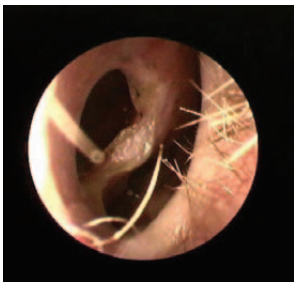

Hình soi lỗ mũi